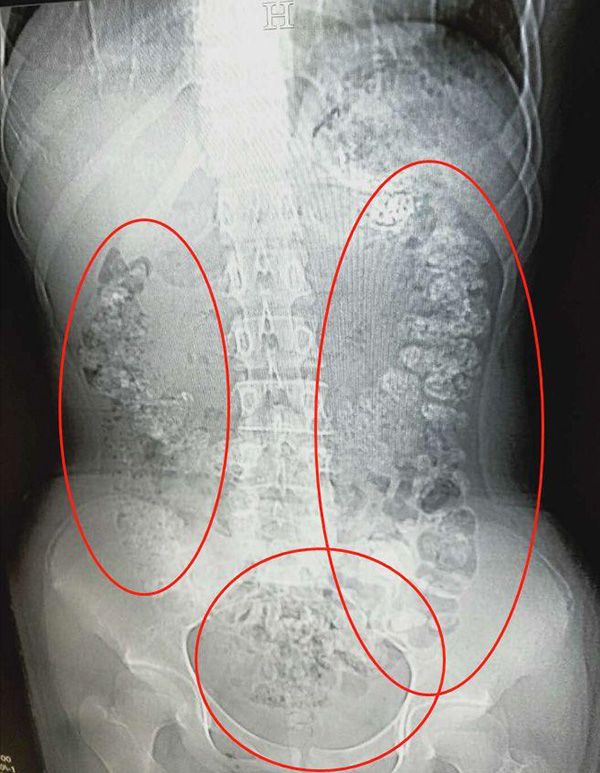

Hasilnya sungguh mengejutkan karena dia menemukan hal yang tak biasa dalam hasil CT Scannya. Dihasil CT Scannya terdapat bola-bola yang berada pada pencernaan gadis ini, dokter menemukan terdapat sekitar ratusan bola tapioka dari bubble tea yang tak dicerna dengan baik.

Ternyata gadis yang tinggaal di provinsi Zhejiang ini mengeluh konstipasi, tak bisa makan, dan menderita sakit perut itu meminum bubble tea dalam 5 hari sebelum dia merasakan sakit pada perutnya. Menurut laporan media China, dikutip dari Asia One, orang tuanya pun mengirim dia ke rumah sakit pada bulan Mei lalu.

Dan akhirnya Zhang Louzhen di rawat oleh dokter karena kecurigaannya bahwa dia sudah mengonsumsi bubble tea dalam jangka waktu yang lama, sehingga kondisinya bisa separah itu.